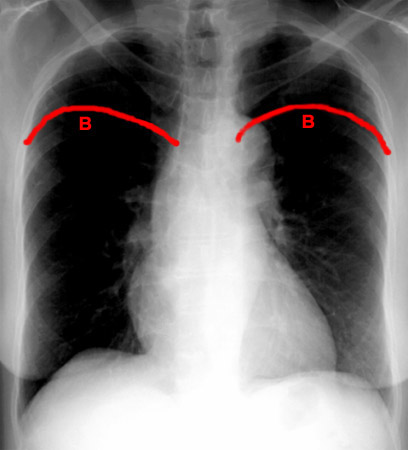

A: Minor Fissure

B: Major Fissure